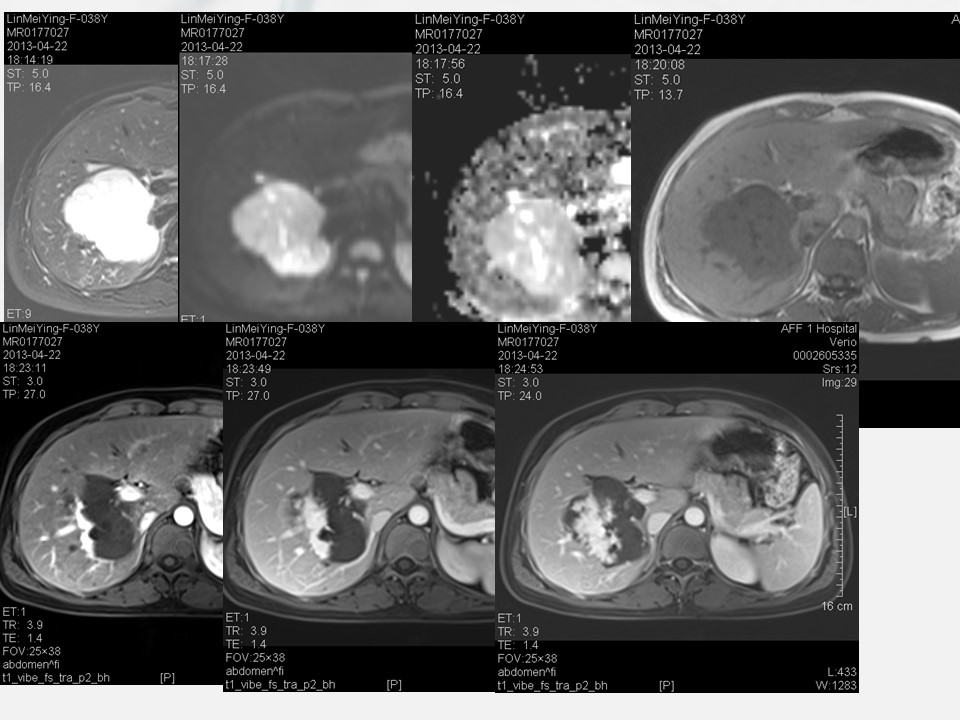

“细菌性肝脓肿的影像诊断” 的相关文章